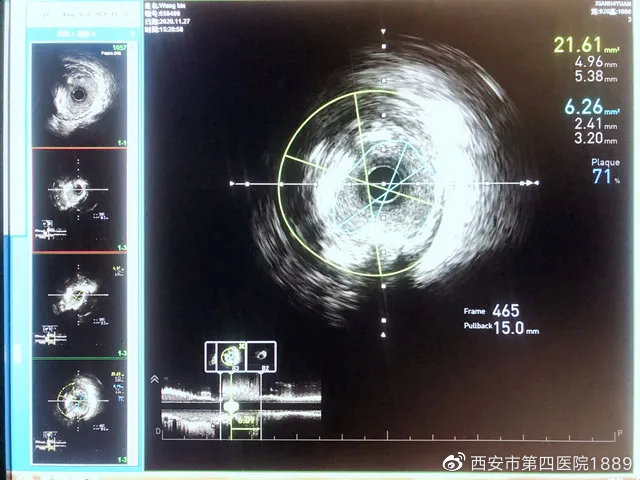

冠状动脉内超声检查术(IVUS)是近年来应用于临床评价冠状动脉病变的一种新的手段。它是在心导管的顶端放置一个超声探头,可发出超声波,在X线透视下沿引导钢丝将超声探头导管插入冠状动脉病变血管段的远端,从血管的远端缓慢撤退导管至近段,对血管横截面进行360°成像,可准确反映病变的性质与程度,同时可以评价介入治疗的效果,弥补了冠脉造影的不足,具有直观、准确的特点,是评价冠心病新的“金标准”。